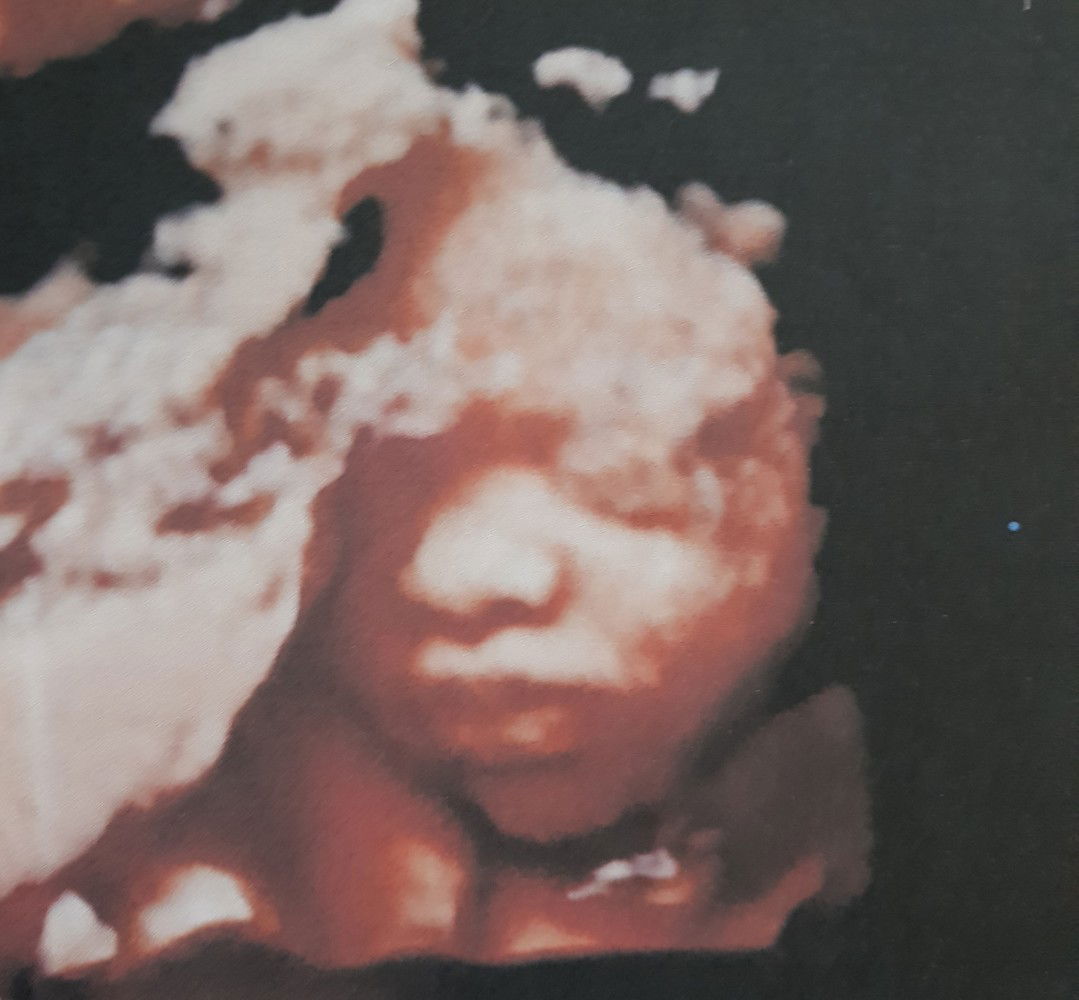

CAS 3D 4D TODAY AT 7 MOS

Grabe nakaka gaan ng loob talaga pag nakita mo na okay si baby bago pa lumabas. God is good grabe nakaka excite na talaga... first time mommy here :) pray lang mommy di tayo papabayaan ni Lord โกโก